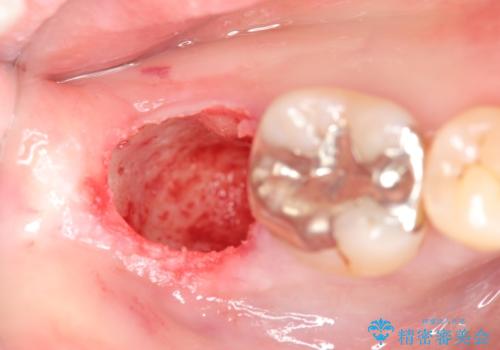

抜歯を余儀なくされる状況ですが、将来的にインプラントによる咬合機能回復を希望されたので抜歯と同時に骨補填剤を填入し骨の造成をしたのちのインプラント治療を計画します。

歯を失い、将来的にインプラントを埋入し咬合機能を回復していく場合、十分な骨量の確保は重要です。

今回抜歯後、骨が十分に確保できないとの判断から抜歯と同時に骨補填剤の填入を行いました。